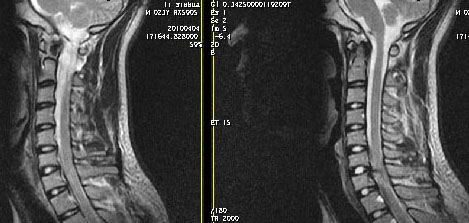

男24岁因一年来感头昏,查体四肢肌力及感觉无异常。颈椎dr未见异常,mri发现c7水平段椎管内左侧占位。患者于7年前有车祸伤病史(但是未检查,自述无异常)。请讨论是否是机化血肿或骨折片,能除外是肿瘤?

椎管内骨性肿块,与第7颈椎左下关节突关系密切,向椎管内生长,第7颈椎椎体左后缘受压变形,边缘可见硬化边,与肿块间间隙清晰。mri扫描肿块内可见骨髓信号,考虑骨软骨瘤可能性大。

考虑c7左侧椎弓根部骨软骨瘤。